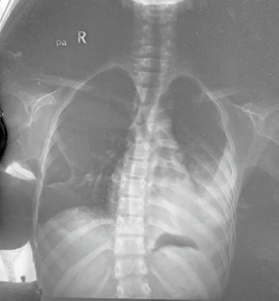

图1 2017年11月7日医院X光片